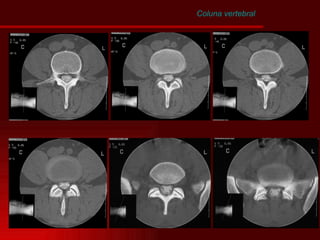

Coluna vertebral Disco Intervertebral Tomografia axial Ressonância Magnética T2

• #14 Representação dos cortes de TC da coluna lombar – identificar estruturas.